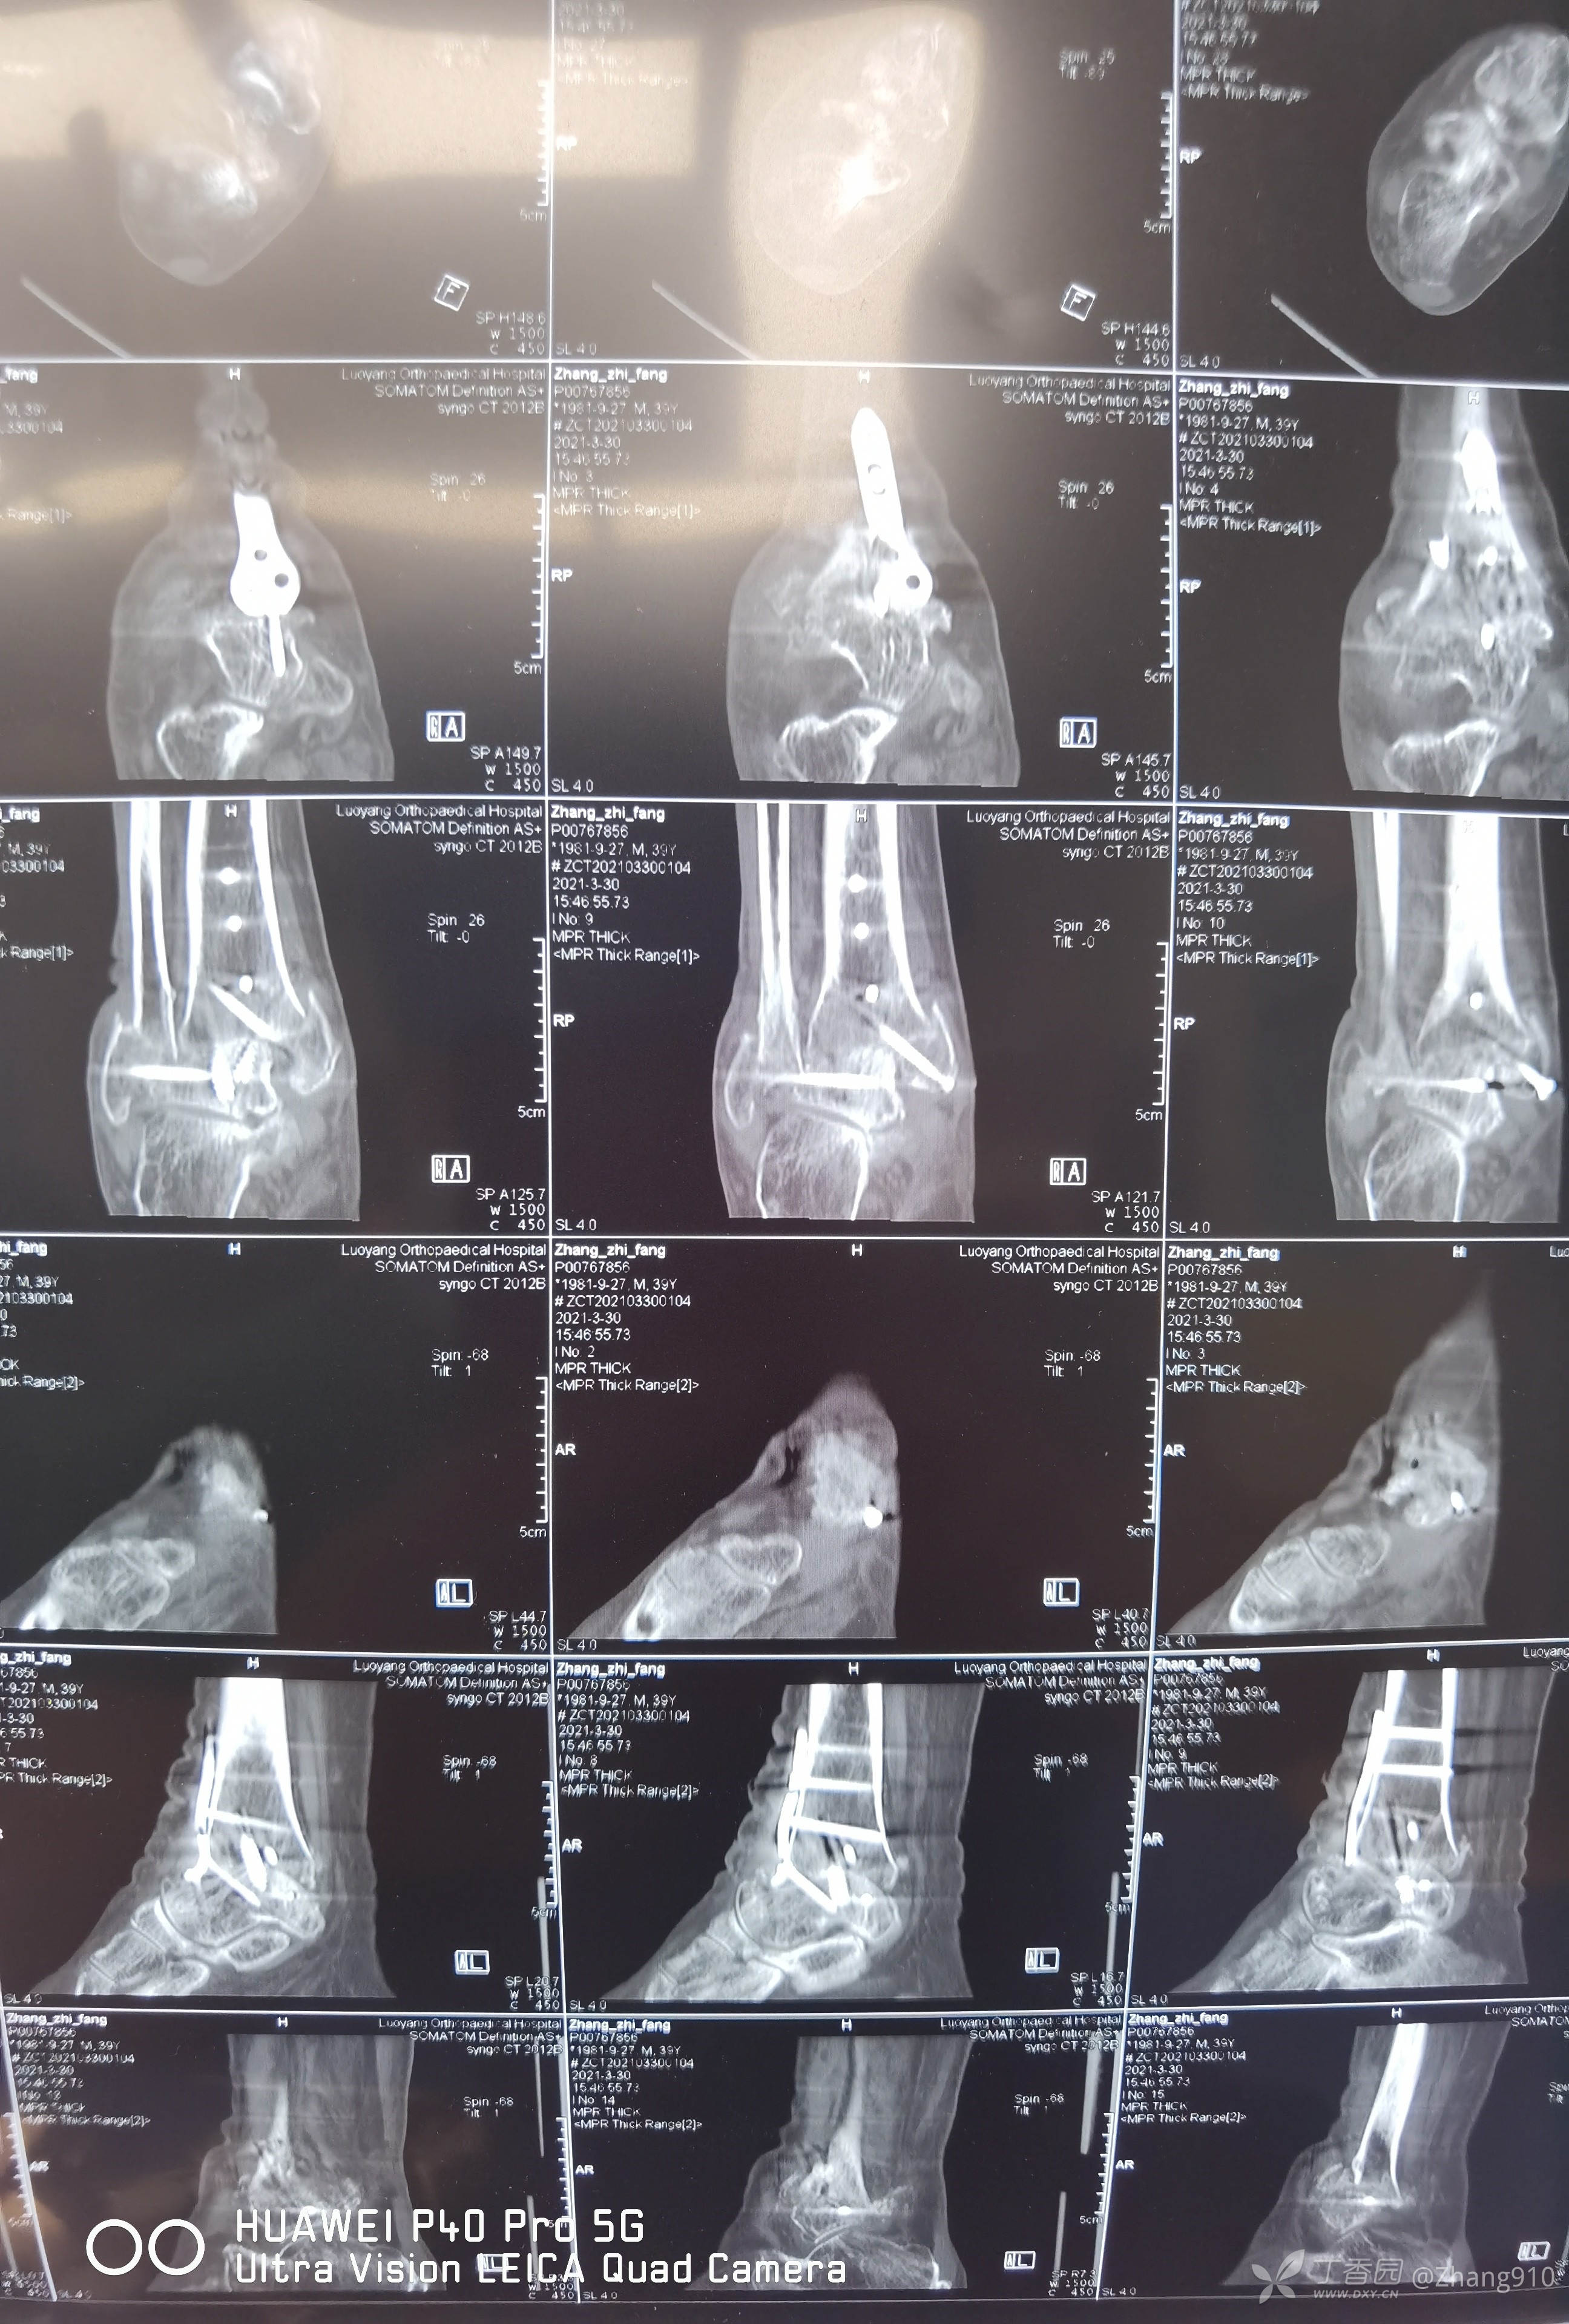

术后复查如下: